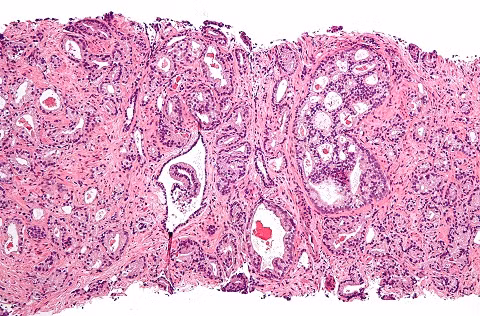

| Ung thư tiền liệt tuyến có thể do di truyền. |